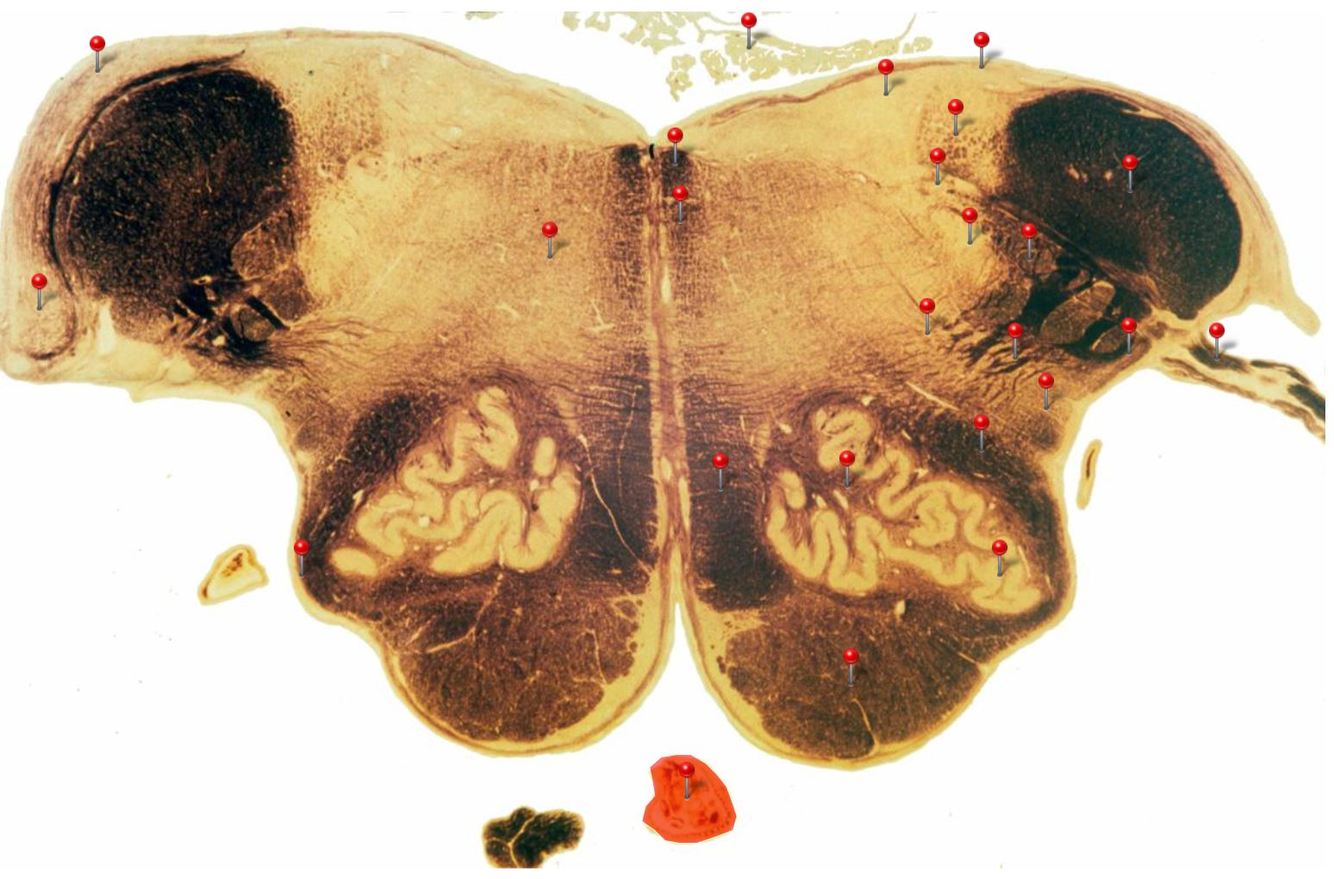

Corticospinal Tract

Rostral Medulla

Controls precision and speed of skilled movements involving the distal muscles of the contralateral limbs, particularly those of the hands and fingers

Nucleus Ambiguus

Neurons supply the muscles of the pharynx, larynx, upper oesophagus and heart

Basilar Artery

Provides blood supply to much of the cerebellum, pons, midbrain and posterior thalamus as well as part of the temporal (inferior surface) and occipital (medial and inferior surfaces) lobes

Olives

Elevations formed by the inferior olivary nuclei which integrate information from a variety of sources before relaying it to the cerebellum

Rubrospinal Tract

Assists in the control of movements of the hands and fingers

Medial Vestibular Nucleus

Process inputs from vestibular receptors of the inner ear and are involved in the regulation of posture and the coordination of head and eye movements

Spinal Trigeminal Tract

Transmits somatosensory (crude touch, pain and temperature) inputs from the Trigeminal nerve (CN V) through the midpons and medulla to the spinal trigeminal nucleus.

Ventral Cochlear Nuclei

One of the relay nuclei for the auditory fibres of the vestibulocochlear nerve (CN VIII) and functions to modify inputs to the higher auditory structures

Medial Longitudinal Fasciculus

Pathway through which eye movements are coordinated with changes in head position

Dorsal Cochlear Nuclei

One of the relay nuclei for auditory fibres of the vestibulocochlear nerve (CN VIII) and functions to modify inputs to the higher auditory structures

Inferior Olivary Nucleus

Plays an important role in the learning of new motor skills

Solitary Nucleus

Processes visceral afferent (GVA and SVA [taste]) inputs from CN VII, IX and X and relays them to the reticular formation and visceral efferent nuclei

Spinal Trigeminal Nuclei

Processes sensory inputs, particularly pain and temperature, from the head and neck and relays them to the ventral posteromedial nucleus of the thalamus

Inferior Vestibular Nucleus

Plays a role in the maintenance of balance and the coordination of eye and head movements

Medial Lemniscus Rostral Medulla Transmits sensations of **discriminative touch, vibration, proprioception** an **stereognosis** from the *gracile* and *cuneate nuclei* to the *ventral posterior nuclei of the thalamus*

Ventral Spinocerebellar Tract Rostral Medulla Provides feedback to the cerebellum concerning motor activity (including reflexes) in the lumbosacral levels of the spinal cord

Glossopharyngeal Nerve (CN IX) Rostral Medulla Transmits taste and tactile sensation from the posterior part of the tongue, pharynx and ear, and visceral sensation from the chemo- and baroreceptors of the carotid body and sinus (also supplies efferent fibres to the otic ganglion and stylopharyngeus m.)

Inferior Cerebellar Peduncle Rostral Medulla Formed by pathways passing in both directions between the medulla and cerebellum

Tectospinal Tract Rostral Medulla Function in humans not precisely determined; thought to mediate reflex movements of head in response to visual and perhaps auditory stimuli

Olivocerebellar Tract Rostral Medulla Transmits information from inferior olivary nucleus to the *contralateral* cerebellum, where it forms the **climbing fibres**

Lateral Vestibular Nucleus Rostral Medulla Contains cell bodies of the (lateral) vestibulospinal tract which regulates the activity of **axial** and **proximal** limb muscles in order to **maintain balance and posture**